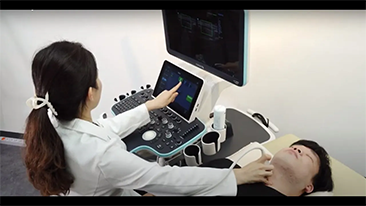

Algemene beeldvorming

Mindray Resona-oplossingen voor algemene beeldvorming helpen clinici bij het realiseren van nauwkeurigere en effici?ntere diagnose- en behandelingsresultaten door middel van sondes voor aparte toepassingen en effici?nte klinische toepassingstools.